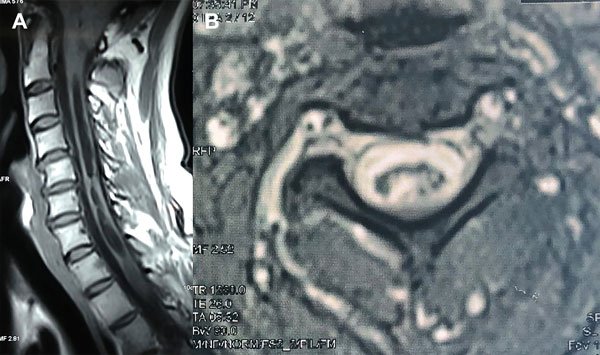

Caso 3: Persistencia sintomática

Una mujer de 55 años consultó por dolor cervical mecánico y adormecimiento del miembro superior izquierdo no evolutivo. El examen neurológico mostró una leve pérdida de sensibilidad táctil en el dermatoma C6 del brazo izquierdo y reflejos vivos en los miembros inferiores. Había sido operada 3 años antes y se le había realizado una descompresión cráneo espinal. La RM mostró una dilatación siringomiélica que involucraba toda la médula cervical con ocupación parcial del canal espinal (Figura 5A) y en los cortes axiales una solución de continuidad a nivel medular compatible con una comunicación siringosubaracnoidea espontánea (Figura 5B). La RM en contraste de fase indicó que las velocidades de circulación del LCR a nivel de la unión cráneo-cervical eran normales. Se hizo el diagnóstico de síndrome post siringomiélico y no fue llevada a cirugía. Fue controlada durante 2 años y el cuadro clínico e imagenológico permanecía estable.

Figura 5: Caso 3. A: RM de columna cervical en plano sagital ponderada en T1, postoperatoria que muestra una siringomielia con ocupación parcial del canal. B: RM de columna cervical en plano axial ponderada en T2 postoperatoria que sugiere una comunicación entre la cavidad siringomiélica y el espacio subaracnoideo.